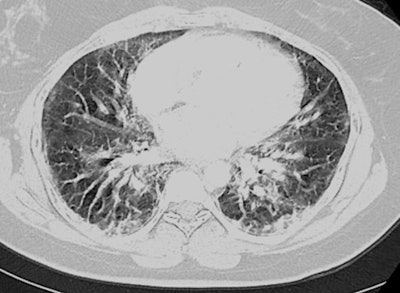

Subsequent chest CT scans revealed that he had multifocal ground-glass and nodular opacities with diffuse interlobular septal thickening, indicative of EVALI. The physicians responded to this finding by giving the patient steroid medication, after which he gradually improved.